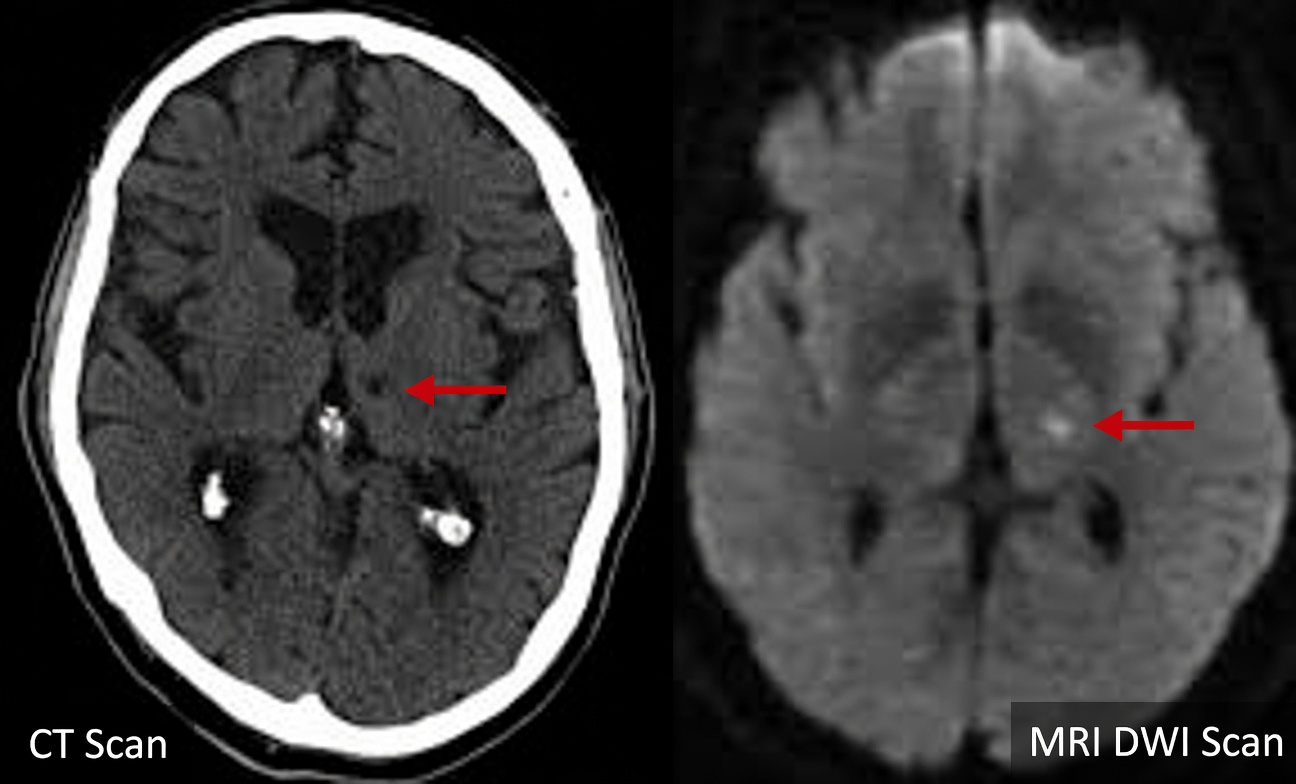

A lacunar stroke happens when a very small artery—sometimes as thin as a hair—gets blocked deep inside the brain. Compared with larger strokes, these events may not cause obvious, dramatic symptoms right away. Research reported in journals such as Stroke and Neurology suggests that 20–30% of adults over 60 show evidence of silent lacunar strokes on brain scans, despite feeling well.

| Brain imaging | Small cavities, white matter changes | Minimal changes | Different patterns (e.g., atrophy, plaques) |